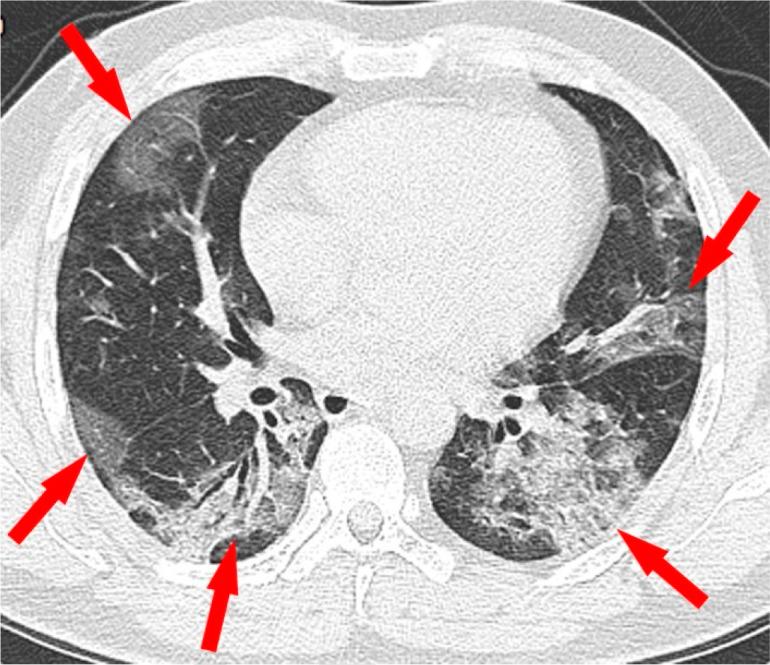

In December 2019, an outbreak of severe acute respiratory syndrome coronavirus 2 infection occurred in Wuhan, Hubei Province, China, and spread across China and beyond. On February 12, 2020, the World Health Organization officially named the disease caused by the novel coronavirus as coronavirus disease 2019 (COVID-19). Because most patients infected with COVID-19 had pneumonia and characteristic CT imaging patterns, radiologic examinations have become vital in early diagnosis and the assessment of disease course. To date, CT findings have been recommended as major evidence for clinical diagnosis of COVID-19 in Hubei, China. This review focuses on the etiology, epidemiology, and clinical symptoms of COVID-19 while highlighting the role of chest CT in prevention and disease control.

2019 年 12 月,中国湖北省武汉市发生了严重急性呼吸综合征冠状病毒 2 型感染的爆发,并在中国乃至全球蔓延。2020 年 2 月 12 日,世界卫生组织正式将由新型冠状病毒引起的疾病命名为 2019 冠状病毒病(COVID-19)。由于大多数感染 COVID-19 的患者都患有肺炎和特征性的 CT 影像学模式,放射学检查在早期诊断和疾病过程评估中变得至关重要。迄今为止,CT 检查结果已被推荐为中国湖北省 COVID-19 临床诊断的主要依据。本综述重点介绍了 COVID-19 的病因、流行病学和临床症状,同时强调了胸部 CT 在预防和疾病控制中的作用。